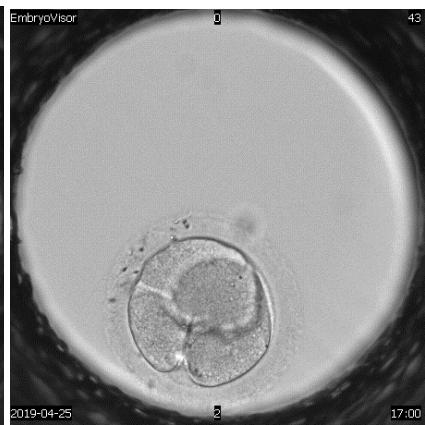

The embryological stage of ART programs is one of the most important, since the assessment of the quality of oocytes, their fertilization and in vitro cultivation to the stage of preimplantation embryos largely determines its success. Morphological evaluation of embryos is the main method of embryo selection. Time-lapse microscopy is one of the modern methods of selecting a high-quality embryo for transfer. In the analysis of many retrospective and prospective studies, they emphasize the advantage and lack of differences compared to traditional morphological assessment of the quality of embryos Almost all publications devoted to timelapse microscopy have focused on determining the timing of specific events of embryo division and then using this information to create algorithms that help to select embryo for transfer.

A detailed view of techniques used to assess human embryo development to enhance reproductive potential.